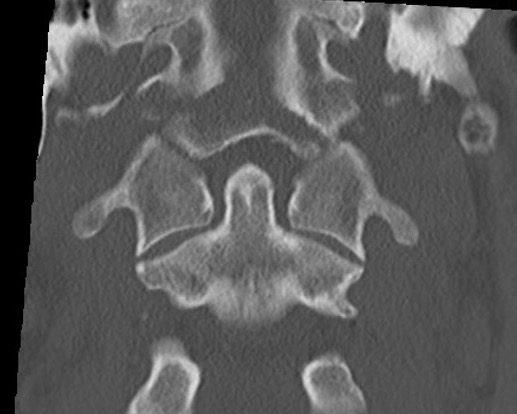

Type II: Occipital condyle fracture involving base of skull

Type III: Inferomedial alar ligament avulsion

Type II: Basal skull involvement